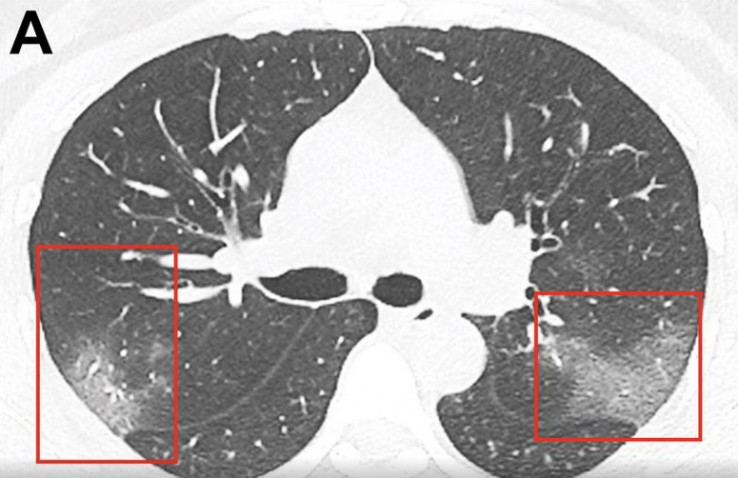

Ljekari su objavili šokantan CT snimak koji najbolje pokazuje šta koronavirus radi plućima.

Na CT snimcima ljekari su uočili bijele sjene, poput takozvanog mliječnog stakla, što ih je upozorilo na to da su pluća djelimično ispunjena tekućinom.

Snimci pluća predstavljeni su u naučnom časopisu "Radiology", a tekst potpisuje grupa ljekara istraživača Prve univerzitetske bolnice u Lanzou.

Navode da kod pacijenata zaraženih koronavirusom dolazi do infekcije koja može oštetiti pluća ili izazvati upalu opasnu po život. Dolazi do oticanja pluća i nagomilavanja tekućine u njima. Pacijenti se zbog toga stavljaju na terapiju lijekovima koji pomažu u otvaranju dišnih kanala.